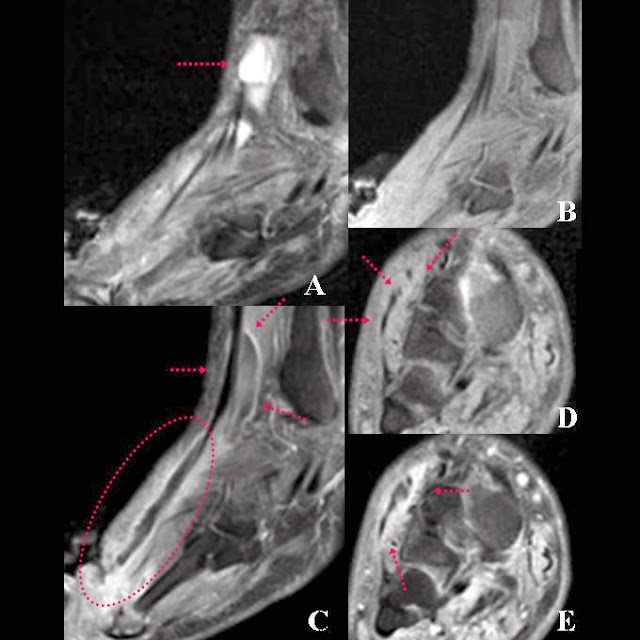

Resonancia Magnetica. Alteración de partes blandas en pie diabetico

Resonancia Magnética

La Resonancia Magnética puede, por sí sola, demostrar con alta certeza si el proceso de infección está limitado a los tejidos blandos o se extendió al hueso.

Los callos óseos plantares tienen una presentación característica por resonancia magnética. Cuando se detectan cambios en el brillo de las imágenes hay que sospechar una infección local. A veces el examen clínico del pie no puede identificar la profundidad del proceso infeccioso, y es allí cuando un examen de resonancia es de extrema utilidad.

Resonancia de ulceración en pie diabetico

La progresión de una úlcera infectada si no se trata en forma agresiva, puede dar lugar a una celulitis severa y complicarse con infección del hueso o de las articulaciones del pie.

Los tendones no son una vía común de diseminación de las infecciones. De tal manera puede encontraste en la Resonancia un engrosamiento y acumulación de líquido en las vainas de los tendones. Luego de administrar agente de contraste las membranas sinoviales inflamadas suelen realzar en forma evidente.

Cuando la osteomielitis (infección ósea) es de evolución crónica, suele ser un proceso más indolente que se manifiesta característicamente por heridas del pie diabético que no terminar de curar correctamente con los tratamientos comunes a través del tiempo.

En estos casos es indicativa la Resonancia Magnética porque puede demostrar con alta certeza si el proceso está limitado a los tejidos blandos o se extendió al hueso. En aquellos casos que requieren amputación como última salida terapéutica, la Resonancia es una herramienta imprescindible para la planificación quirúrgica, aclarando los límites de resección en la cirugía y facilitar el plan quirúrgico previo a una amputación para realizar una cirugía  lo más conservadora posible a la vez que exhaustiva.

Tenosinovitis infecciosa. Imagen de Resonancia Magnética